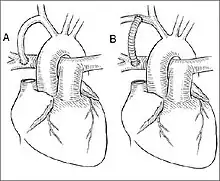

Blalock–Taussig Shunt – left subclavian artery to left pulmonary artery.

Blalock–Taussig Shunt – left subclavian artery to left pulmonary artery.